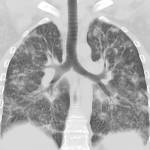

Грибковую пневмонию выявляют благодаря анализу жалоб и результатов дополнительных методов исследования – в первую очередь рентгенологических.

Инструментальные методы в большинстве случаев позволяют установить сам факт воспаления легких, но на его грибковую природу не указывают. Привлекаются:

- рентгенографическое исследование грудной клетки в двух проекциях – на рентгенограммах выявляют очаги затемнения;

- компьютерные методы – компьютерные срезы позволяют выявить небольшие очаги поражения, «спрятанные» глубоко в паренхиме легких. Привлекают компьютерную томографию (КТ) и мультиспиральную компьютерную томографию (МСКТ), которая является усовершенствованной версией КТ;

- магнитно-резонансная томография (МРТ) – цели те же, что и при проведении компьютерных методов, но информативность и точность выше, так как МРТ более информативна при изучении мягких тканей;